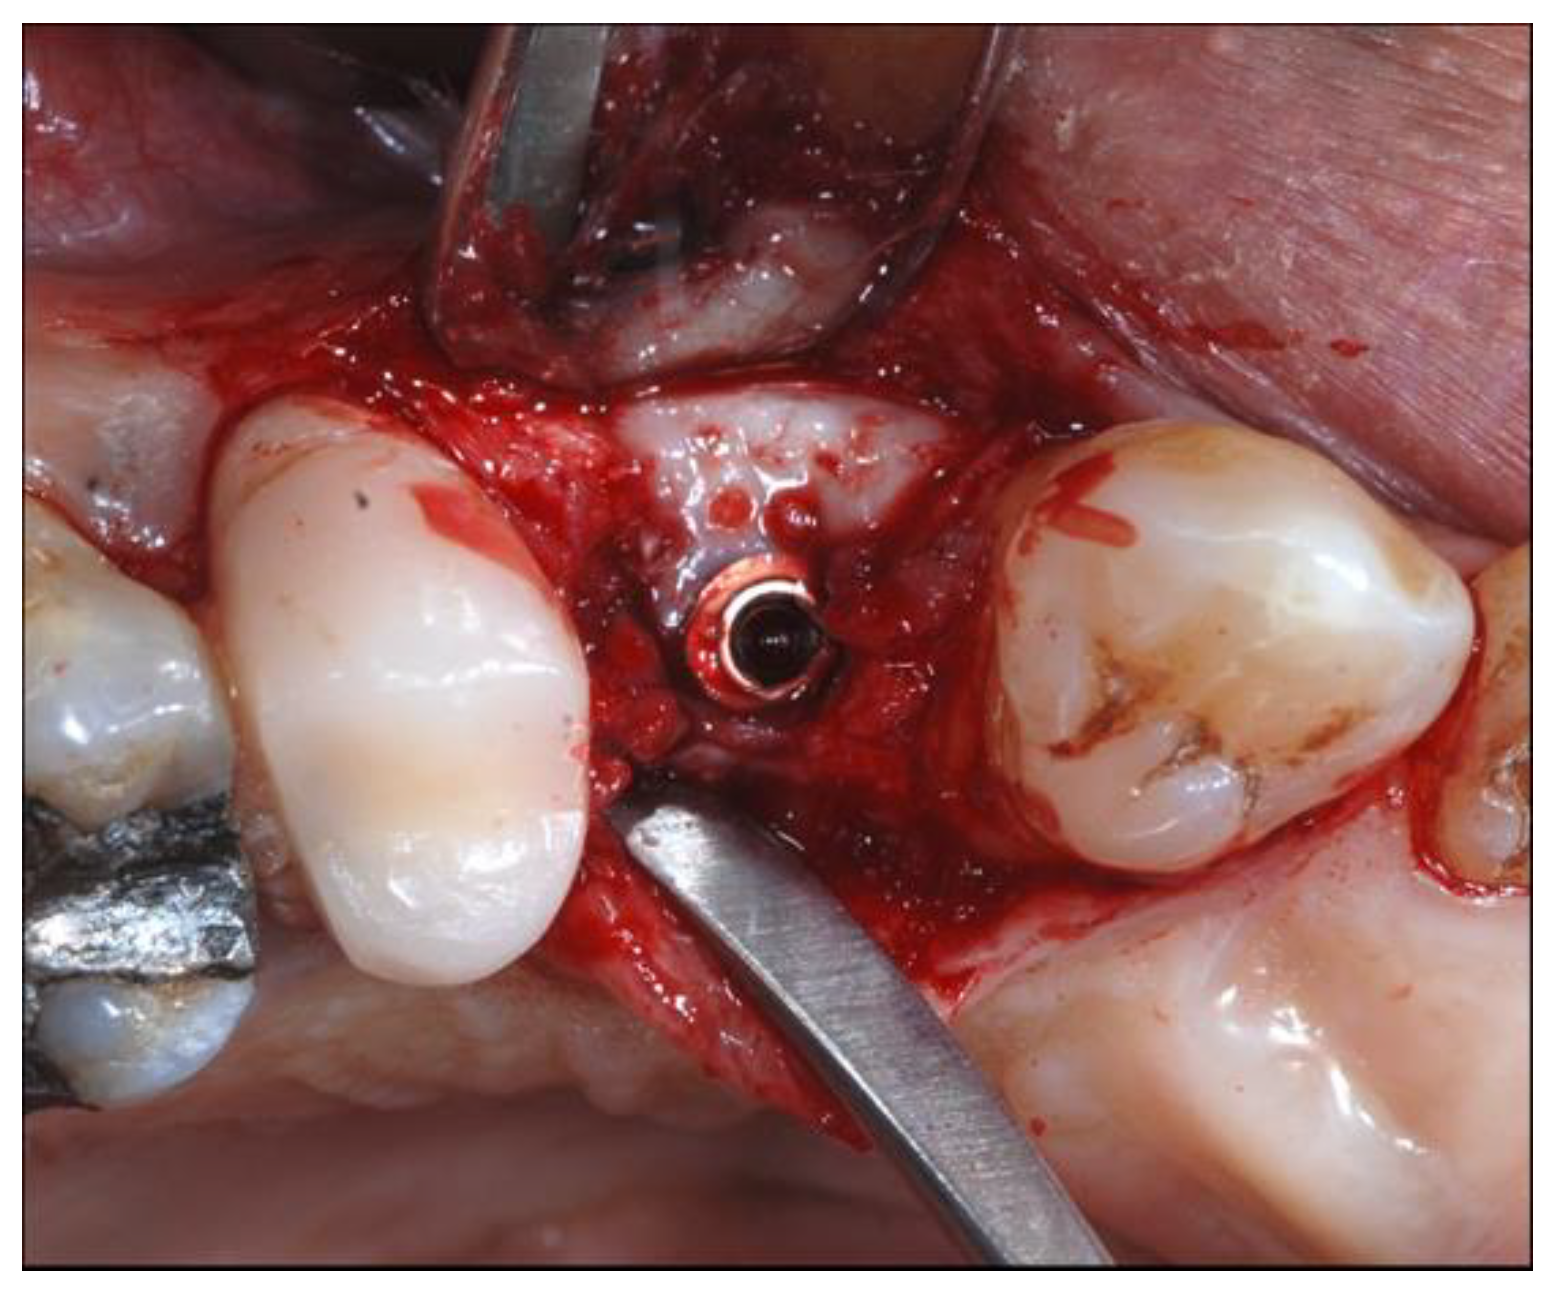

2.4. Surgical Phases

2.5. Re-Entry Surgery and Prosthetic Phases